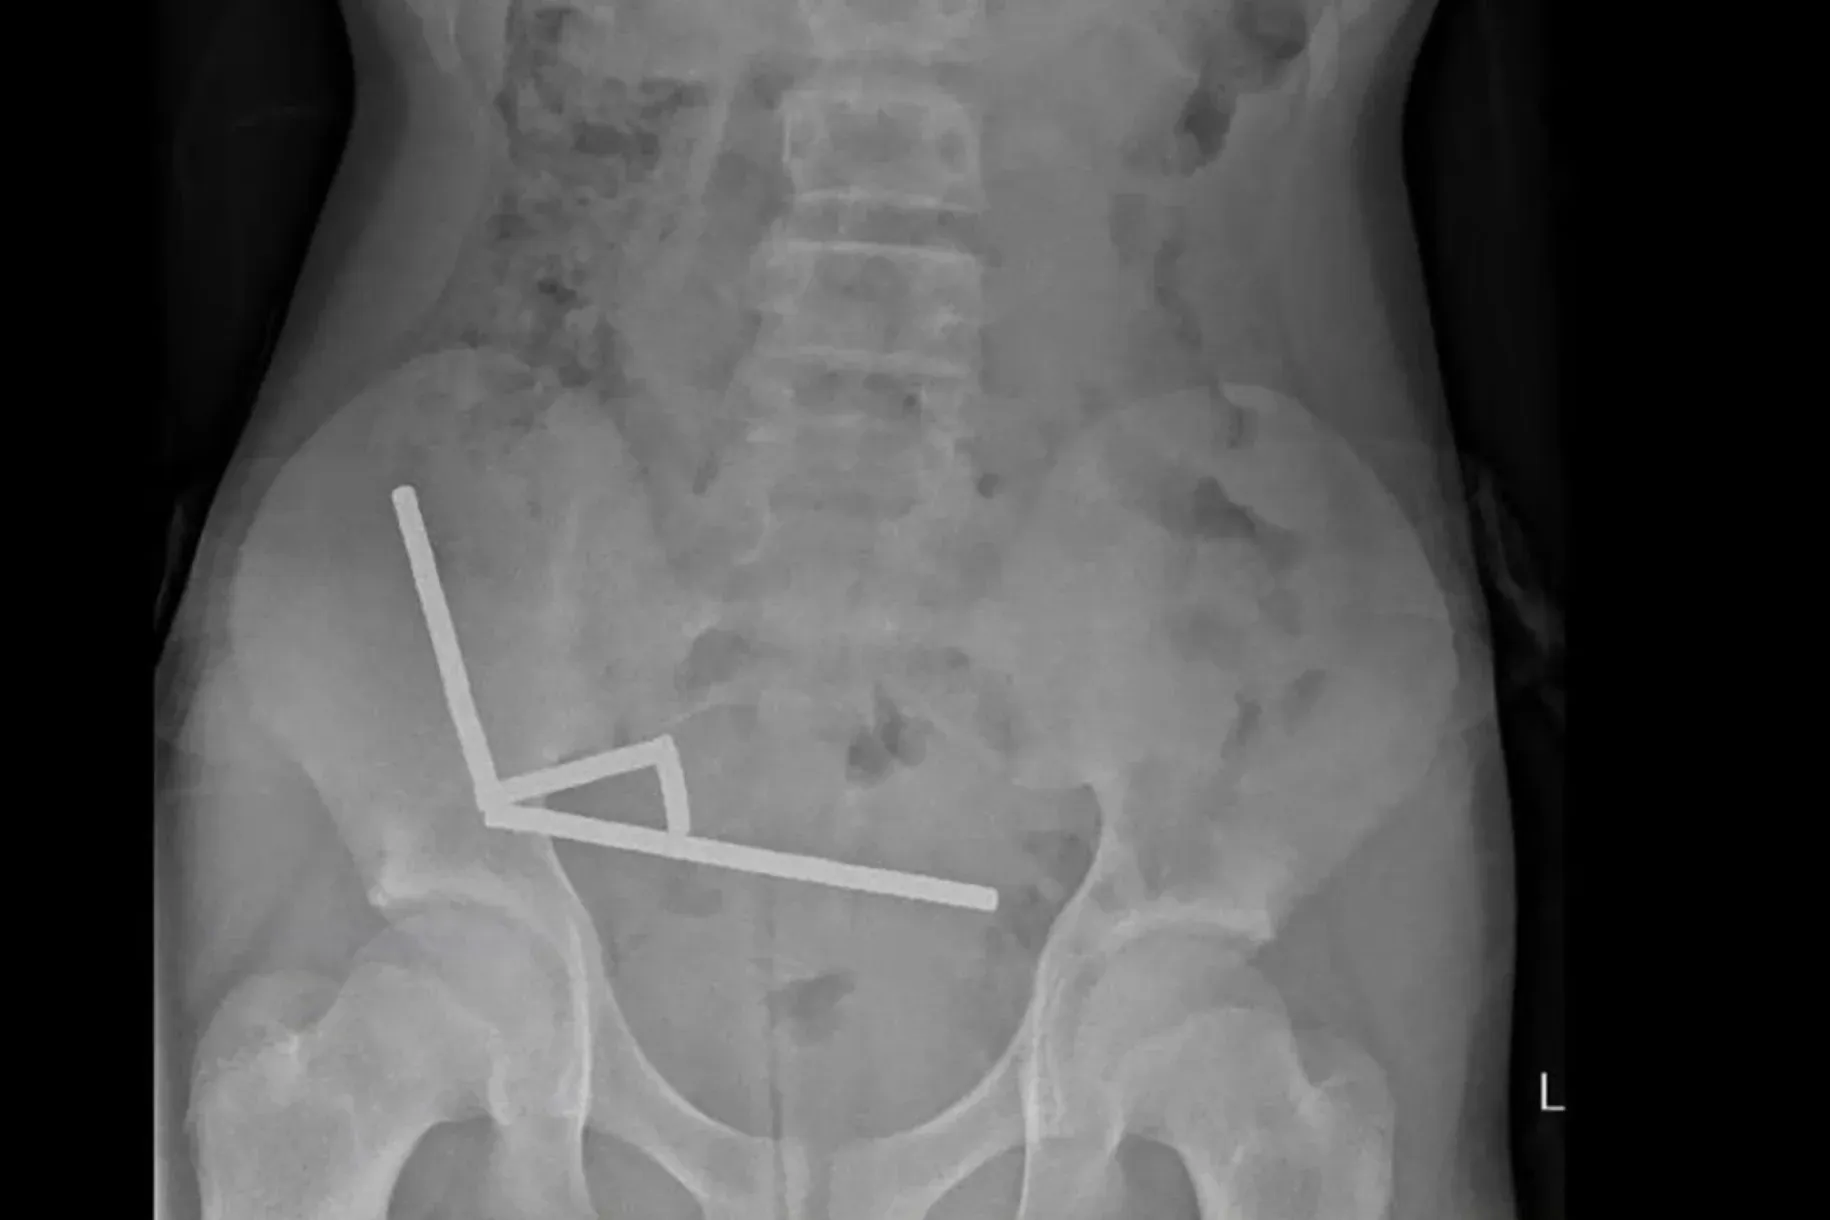

Egy 13 éves új-zélandi fiú száz darab erős mágnest nyelt le, amelyeket a Temuról rendelt, végül négy nap szenvedés után